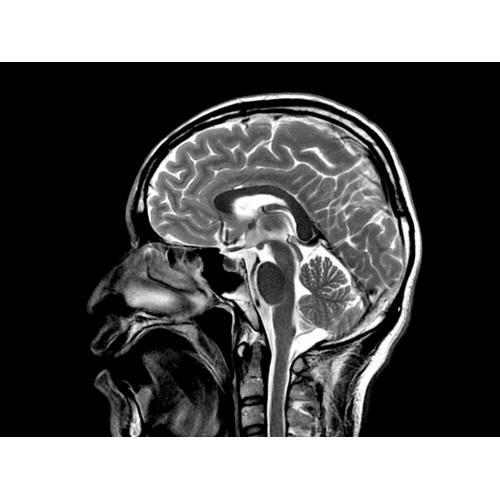

МР-томограф Optima MR450w позволяет получать изображения исключительно высокого качества, которые помогают установить диагноз. Чтобы удовлетворить ожидания клиентов в отношении высокого качества, в МР-томографе Optima MR450w были сохранены дополнительные возможности платформы Discoverу, привнесшие в его работу универсальность и мощь.

• Цифровой РЧ-приемник OpTix — эксклюзивная оптическая РЧ-система увеличивает четкость сигнала и его интенсивность, формируя чистые и резкие изображения.

• Широкое поле зрения — поле зрения шириной 50 см позволяет охватывать крупные анатомические области за меньшее число сканов.